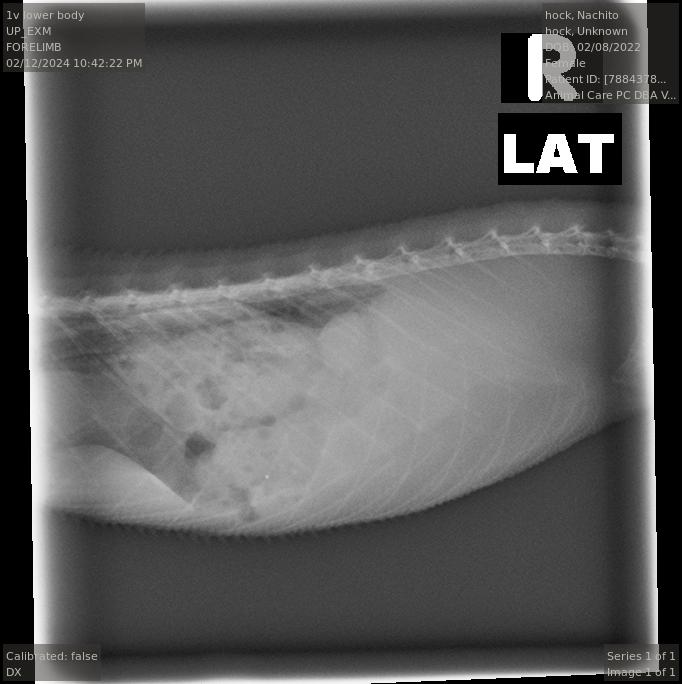

Heres the xray again from the visit, everything was normal with the follicles.